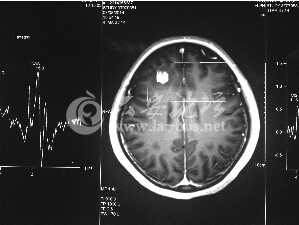

今年6月份,张敏在宿舍休息时,又发起了癫痫,也是口吐白沫,浑身抽搐。送到苏州一家大医院,头颅核磁共振检查出,张敏大脑右额叶处有一处病灶,也就是大脑额头处有个东西。

专家认为有可能是脑瘤,但也有可能是其他的东西,具体是什么,却没有办法进一步判断。医院开了一点控制癫痫的药物,让张敏服用,并叮嘱随时复查。

脑袋里的东西,到底是肿瘤还是其他什么东西,这个谜像个石头一样,压得张敏一家人喘不过气。7月份,张敏一家又来到南京脑科医院求医,第三次检查后,医生觉得很像是寄生虫。不过,影像的检查,只能作为医生推测的依据,具体是什么,只有手术拿出来后才能知道。